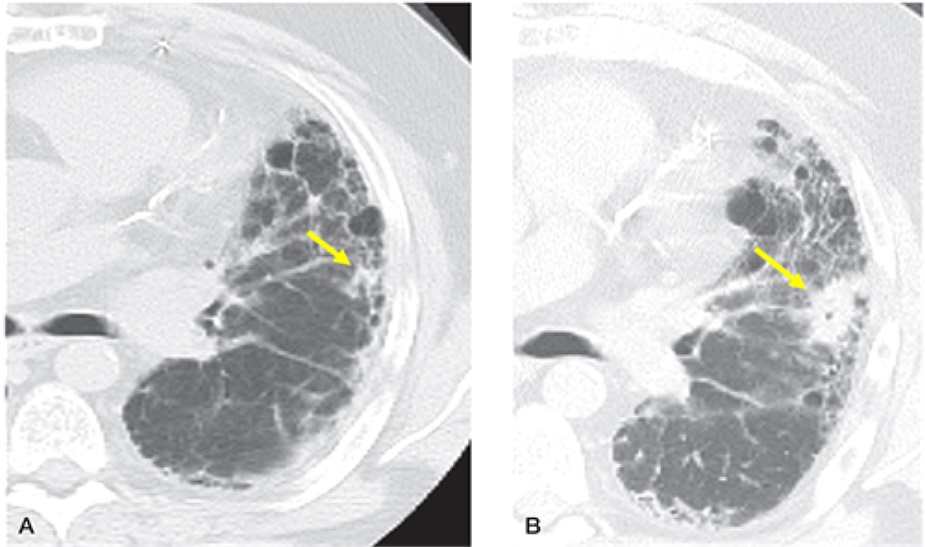

鱗狀細胞癌與腺癌為最常見的肺癌類型,較常以接近纖維化區域的「肺結節」來表現。其預後相關的研究受到追蹤時間、疾病嚴重程度、癌症治療方式不同或有干擾,但多數研究顯示,同時患有肺癌與肺纖維化患者的存活率(19~38.7個月)比沒有罹患肺癌的肺纖維化患者(48~63.9個月)明顯較差。大約10%肺纖維化患者死於肺癌。約75%肺癌發生在肺纖維化區域內或附近,主要發生於下肺葉。詳細檢查纖維化區域並與先前的影像進行比較,對於發現早期肺癌很重要。正子斷層掃描(PET-CT)通常有助於區分與纖維化相關的肺癌和局部纖維化。

特發性肺纖維化-CT發現左下肺葉有一不規則小結節(圖A),四年後明顯變大(圖B),確診為肺癌。High-Resolution CT of the Lung (2021)